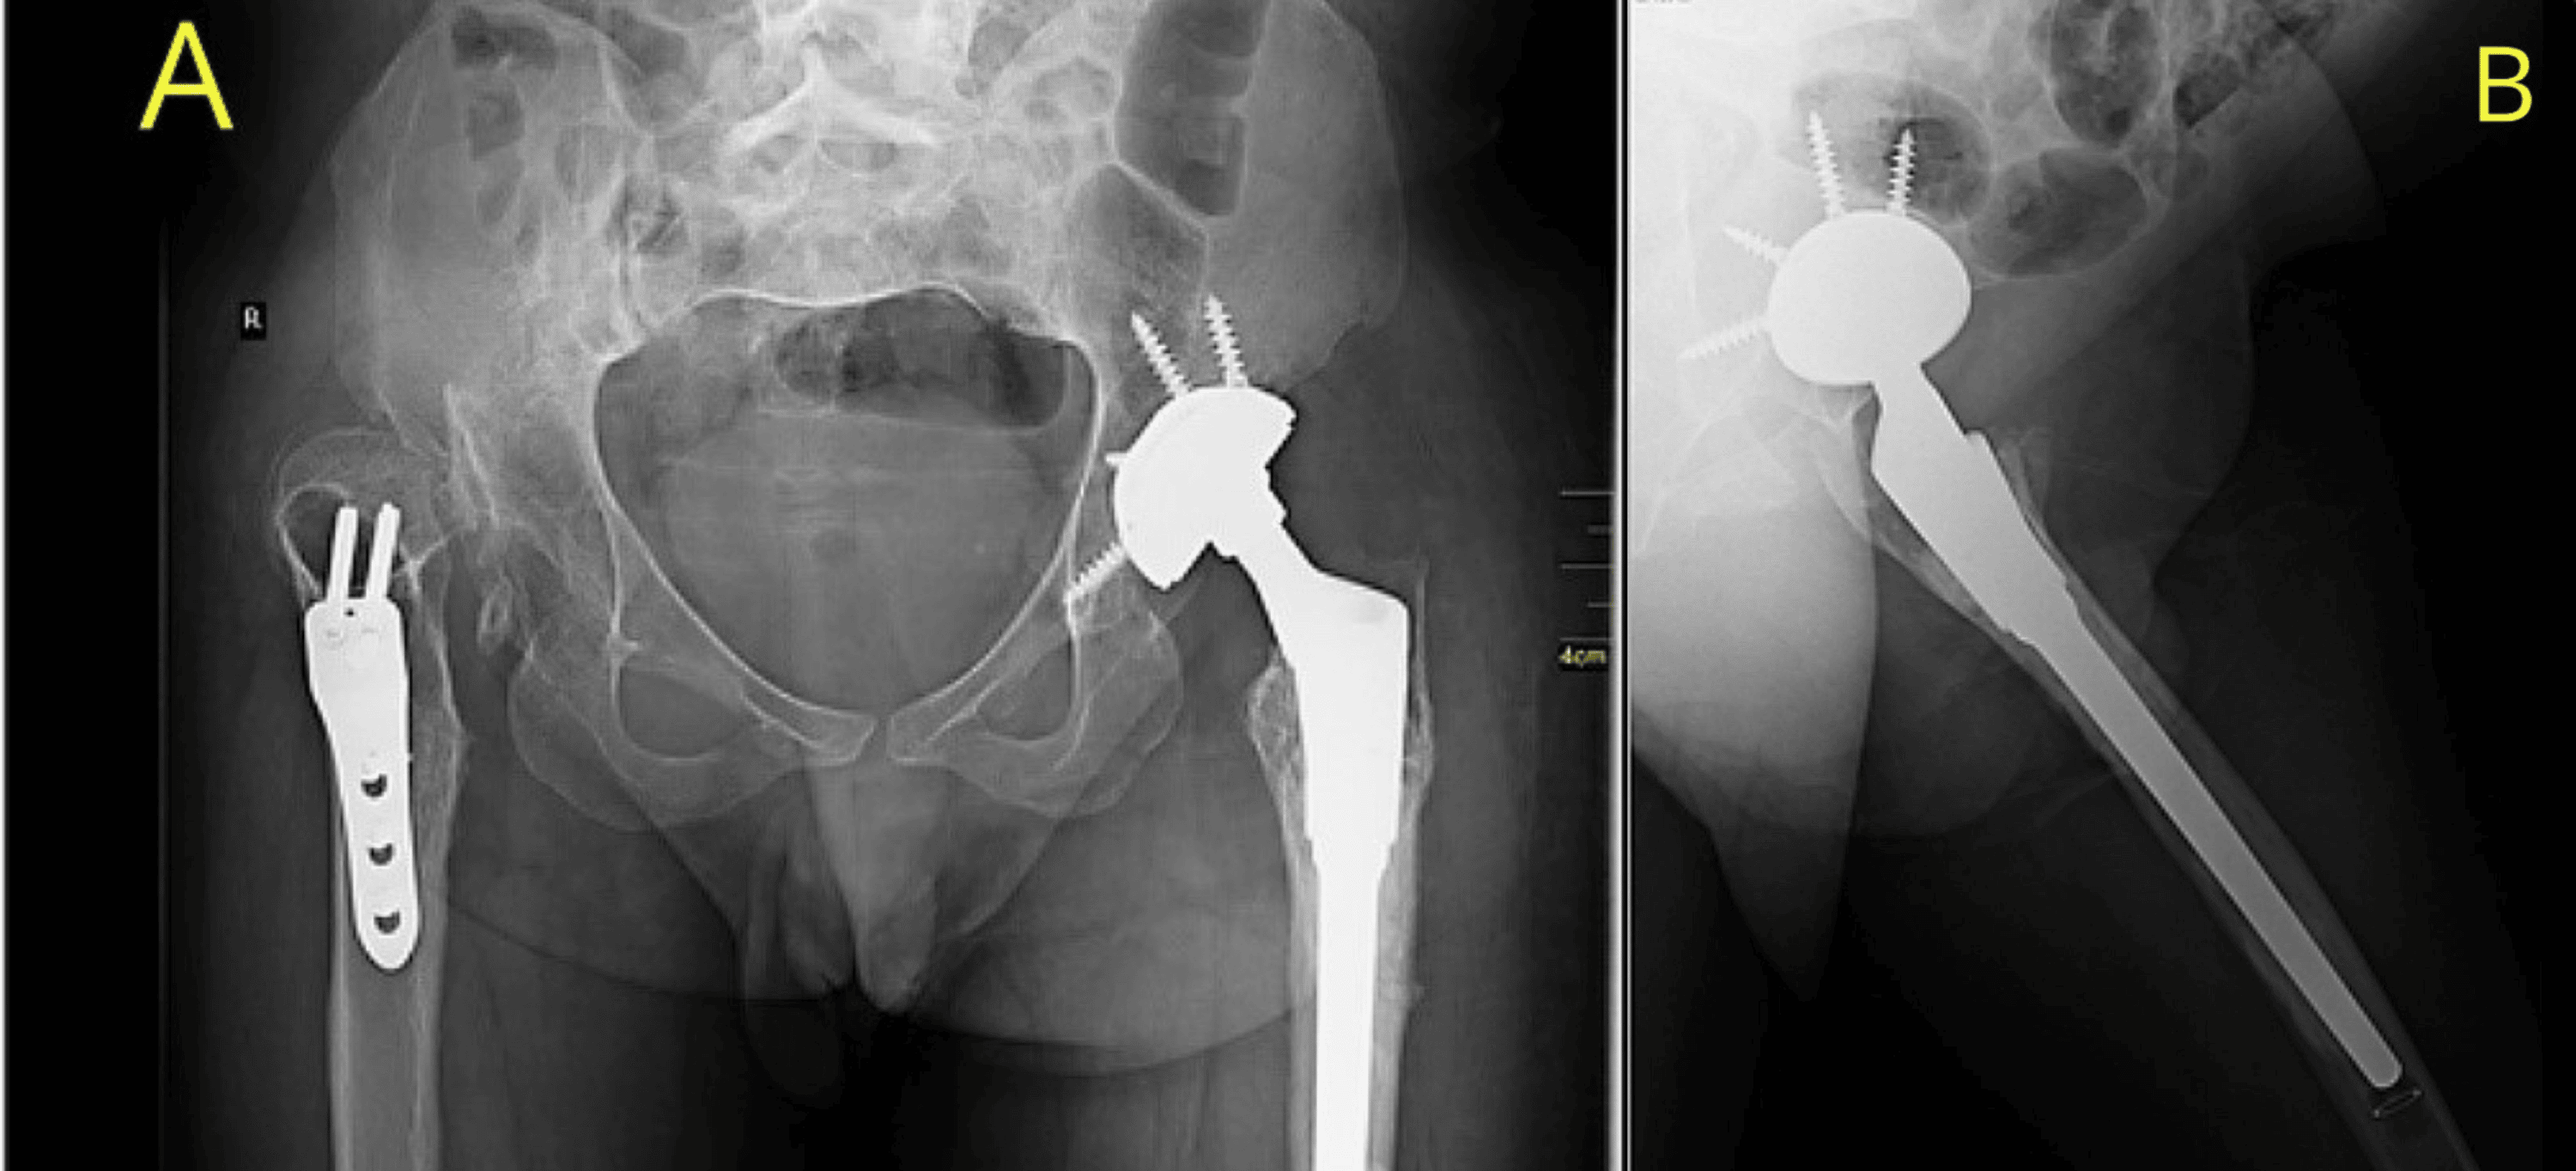

From www.semanticscholar.org

Figure 1 from Total Hip Arthroplasty in Athetoid Cerebral Palsy Semantic Scholar Hip Replacement Cerebral Palsy total hip arthroplasty (tha) is a successful treatment for hip osteoarthritis secondary to hip dysplasia. total hip arthroplasty (tha) is a commonly performed procedure to address degenerative changes of the hip and has been shown. the treatment of the painful hip in cerebral palsy by total hip replacement or hip arthrodesis we found that total hip. Hip Replacement Cerebral Palsy.

Figure 1 from Sciatic nerve palsy after total hip replacement. Semantic Scholar Hip Replacement Cerebral Palsy total hip arthroplasty (tha) is a successful treatment for hip osteoarthritis secondary to hip dysplasia. total hip replacement surgery is a safe and effective treatment strategy for patients with cerebral palsy, offering a significant improvement. in children with cerebral palsy, this hip problem can result in pain when sitting in a wheelchair or with walking, or may. Hip Replacement Cerebral Palsy.

Figure 1 from The treatment of the painful hip in cerebral palsy by total hip replacement or hip Hip Replacement Cerebral Palsy the treatment of the painful hip in cerebral palsy by total hip replacement or hip arthrodesis total hip arthroplasty (tha) is a commonly performed procedure to address degenerative changes of the hip and has been shown. we found that total hip replacement in patients with cerebral palsy is associated with a high degree of patient. total. Hip Replacement Cerebral Palsy.

From www.cureus.com

Optimizing Hip Replacement Procedure in Cerebral PalsyRelated Spastic Hip Dysplasia A Case Hip Replacement Cerebral Palsy we found that total hip replacement in patients with cerebral palsy is associated with a high degree of patient. total hip arthroplasty (tha) is a successful treatment for hip osteoarthritis secondary to hip dysplasia. in children with cerebral palsy, this hip problem can result in pain when sitting in a wheelchair or with walking, or may even.. Hip Replacement Cerebral Palsy.

From www.researchgate.net

Constrained total hip arthroplasty in a paediatric patient with cerebral palsy and painful Hip Replacement Cerebral Palsy total hip arthroplasty (tha) is a commonly performed procedure to address degenerative changes of the hip and has been shown. in children with cerebral palsy, this hip problem can result in pain when sitting in a wheelchair or with walking, or may even. we found that total hip replacement in patients with cerebral palsy is associated with. Hip Replacement Cerebral Palsy.

Figure 3 from The treatment of the painful hip in cerebral palsy by total hip replacement or hip Hip Replacement Cerebral Palsy in children with cerebral palsy, this hip problem can result in pain when sitting in a wheelchair or with walking, or may even. total hip arthroplasty (tha) is a successful treatment for hip osteoarthritis secondary to hip dysplasia. the treatment of the painful hip in cerebral palsy by total hip replacement or hip arthrodesis we found. Hip Replacement Cerebral Palsy.